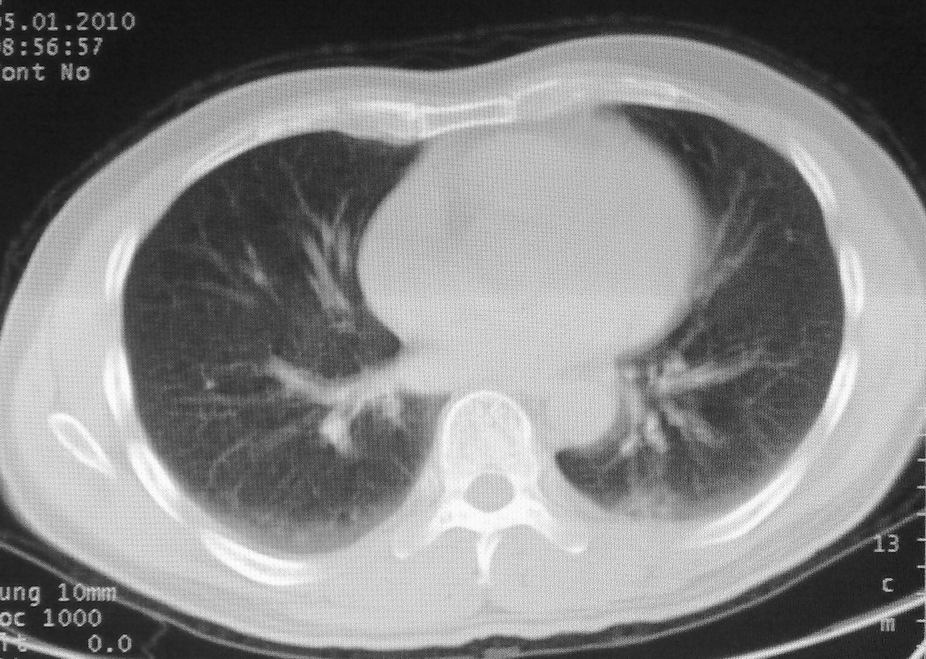

男,51岁,左胸前区不适数天。

薄壁空洞,边缘毛刺,胸膜凹陷,考虑肺癌,结核不排除。

考虑左肺下叶感染性病变。

考虑左肺下叶感染性病变,不除外肺栓。